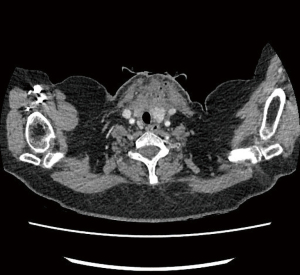

We present a case of early postoperative wound and superior mediastinum infection occurred in our unit.

This 52-year-old lady was referred for a diagnostic mediastinoscopy after routine CT follow up of previously treated breast cancer revealed new mediastinal lymphadenopathy. She underwent cervical videomediastinoscopy and biopsy of stations 2L and 4R lymph nodes. Upon biopsy of 4R, white fluid was drained and this was sent for culture. The patient was discharged on the same day as per our practice. Two days later she was brought back to the hospital as her lymph node sample had grown Streptococcus oralis and Streptococcus anginosus bacteria so she was started on oral ciprofloxacin (fluoroquinolone) accordingly to microbiology advice. On review a week post-surgery, at the end of the ciprofloxacin course, she was found to have a swollen fluctuant wound which was tender on palpation. A CT scan showed a collection containing gas loculi in the anterior neck measuring 50 mm ×48 mm extending inferiorly into the superior mediastinum. She underwent re-exploration of the wound and washout of the mediastinum the following day. After a course of intravenous antibiotics, she was discharged home to continue a prolonged course of oral antibiotics (penicillin and clavulanic acid combination), she made a full recovery (Figure 3).